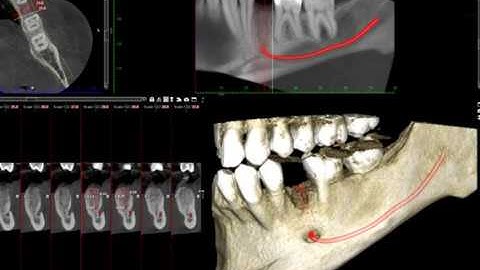

Why a cone beam CT scan analysis is a must before planning maxillary bone grafting for cleft patient